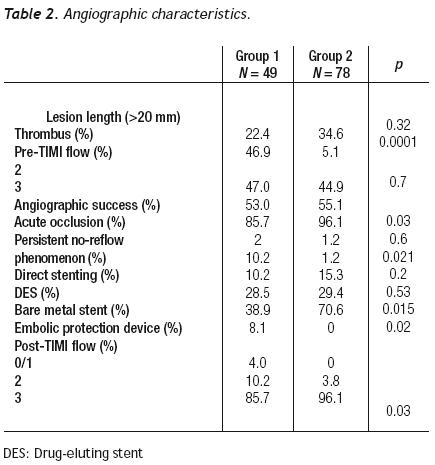

Angiographic success was better in group 2 (85.7% vs. 96.1%, p = 0.03), without differences in the rate of acute occlusion between both groups. IIb/IIIa inhibitors were used in 42.8% of patients with SVG intervention and in 11.5% of the native coronary artery intervention group. The number of treated lesions was 1.02 ± 0.24 for group 1 and of 1.47 ± 0.65 for group 2 (p=0.33). The average length of the lesion was similar in both groups (p = 0.32). The left anterior descending artery was treated in 55.9% of group–2 patients; of these, 70.4% had proximal segment involvement; in this group, a protected left main was treated percutaneously in 18 patients. In group 1, seven stents were covered with expandable polytetrafluoroethylene (PTFE) and nine with bovine pericardium, No differences existed between the groups in the number of lesions treated with drug–eluting stents (DES) and those with direct stenting. A distal protection device was used in 8.1% of group–1 patients (Table 2).

No–reflow phenomenon. The incidence of persistent no–reflow was higher in group 1 (10.2% vs. 1.2%, p = 0.021). The estimated risk of the no–reflow phenomenon when performing PCI of a SVG was OR = 11.0 [(95% IC, 2.32–52.14), p = 0.0001]. IIb/IIIa inhibitors showed no benefit in the SVG stenting group. No–reflow phenomenon was not observed when direct stenting was performed or in whom the distal protection device was used. In the population as a whole, the no–reflow phenomenon was an independent predictor of MACE at 36 months (OR 5.63, 95% IC 1.32 – 23.92, p = 0.019).